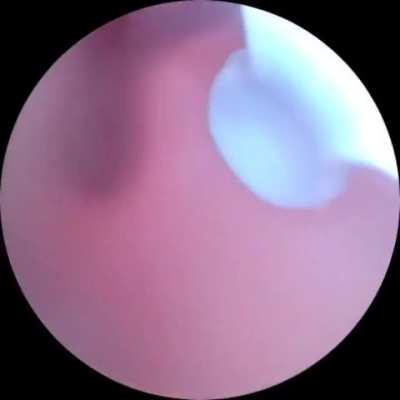

During lock down, I was bitten by a False Widow Spider on my Calf, it got a secondary infection that needed draining and a 2 months of Antibiotics to rid the infection fully. It has left me with a 2” circular dent in my muscle, that even now sinks down a